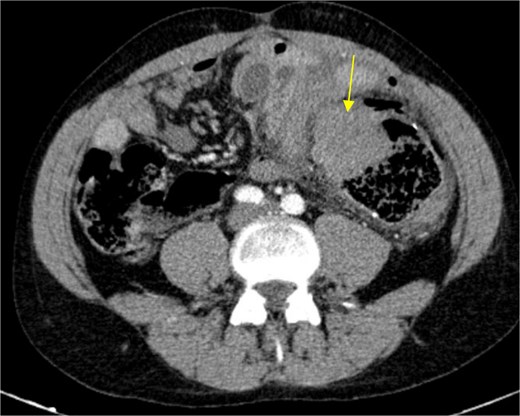

The patient presented at our Emergency Department with a sudden, diffuse, intense abdominal pain. Upon physical examination, the patient’s blood pressure was measured at 132/76 mmHg, heart rate of 103 bpm and a temperature of 39.4°C. The abdominal examination showed a rigid abdomen, with diffuse tenderness, suggesting an acute abdomen scenario. Laboratory tests revealed elevated inflammatory parameters. A abdominal and pelvic computed tomography scan revealed pneumoperitoneum and free fluid in the right iliac fossa and pelvis (Fig. 1). An exploratory laparotomy was proposed and the intraoperative findings included a sigmoid colon perforation with faecal peritonitis. They proceed with sigmoidectomy and temporary abdominal closure, planning for a reintervention to restore gastrointestinal continuity. This was done, after 48 h, through mechanical latero-lateral colo-colic anastomosis. The histopathological examination confirmed diverticulosis with perforation. The patient was subsequently transferred to the intensive care unit, for 5 days. Posteriorly, he developed severe left lumbar pain and hypertension unresponsive to medication. A CT scan revealed left kidney acute ischemia due to left renal artery thrombosis (Fig. 2). Broad-spectrum antibiotic therapy and anticoagulation, was initiated, after assessment by the Vascular Surgery and Urology teams. During his hospitalization, the patient experienced additional thrombotic events, such as occlusion of the left radial artery, and right lower lobar pulmonary embolism. A workup for prothrombotic conditions was conducted, including tests for thrombophilia, lupus, cardiolipins, antinuclear antibody, total protein test, and immunoglobulins, all of which were negative. An angiography of the abdominal aorta revealed arterial microaneurysms in the splanchnic territories: hepatic, perigastric and mesenteric arteries, suggesting polyarteritis nodosa (Fig. 3). Echocardiogram showed no abnormalities. The patient also underwent a study of the left shoulder due to repetitive pain complaints, with a suspected rupture of the rotator cuff. Electromyography excluded peripheral nerve damage. No other complications were reported. The patient was discharged on the 21st day after surgery, under anticoagulation therapy and steroids due to a suspected diagnosis of polyarteritis nodosa. Twenty-seven days after surgical intervention, the patient returned to the ED, presenting with abdominal pain in the lower quadrants and nausea. He was hemodynamically stable with abdominal pain and tenderness on the left flank and iliac fossa. Laboratory tests revealed leukocytosis and hyperlactacidemia. The CT scan reported free fluid, free gas bubbles adjacent to the sigmoid which had a concentric circular thickening of the wall, just distal to the previous anastomosis (Fig. 4). An exploratory laparotomy was performed, during which a large hematoma on the wall of the left colon was identified, with no apparent signs of perforation. A peritoneal lavage, drainage, and a derivative ileostomy were carried out. During the post-operative period the patient maintained a small volume of purulent discharge through the abdominal drain, with no abdominal tenderness. A reevaluation CT scan was performed, highlighting a regression of the hematoma of the colonic wall but raised suspicion of a low output fistula near the anastomosis. Since the patient maintained hemodynamic and analytical stability, he was discharged from the hospital with home care, including an abdominal drain, parenteral nutrition, empirical antibiotic therapy, and gradual reduction in the steroid dosage. The patient was referred to the ED, on Day 6, due to enteric drainage. An enterocutaneous fistula was diagnosed, and he was readmitted. He received 12 days of full-dose parenteral nutrition, which reduced the fistula output and improved his clinical and analytical status. Due to residual drainage volume and an analytical and imagiologic improvement, the drain was removed, and the patient was discharged, tolerating an oral diet, and with a functioning ileostomy.

Circular densification of the sigmoid colon wall, distal to the previous anastomosis (arrow).